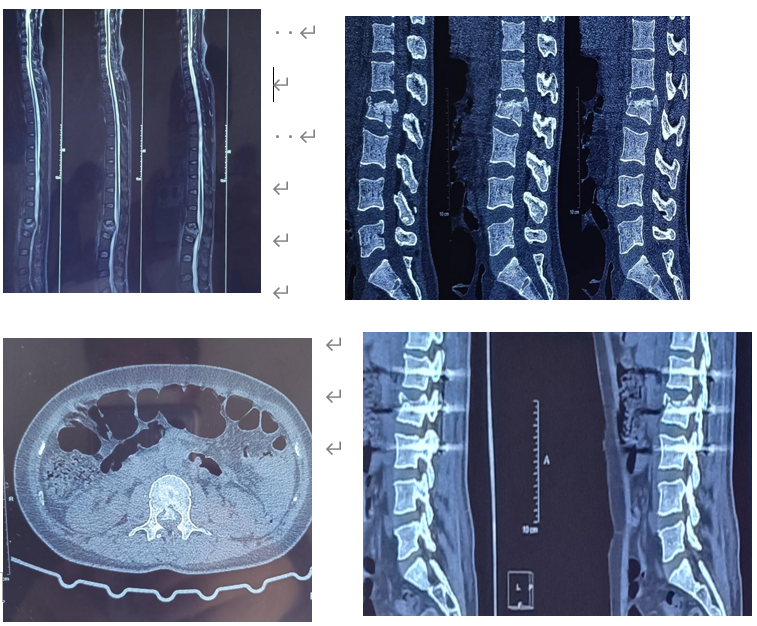

A医院2021年12月21日CT(№XX、姓名黄某某)示:腰2椎体爆裂性骨折,可见骨块突入椎管,相应处椎管明显狭窄;

A医院2021年12月22日MRI(№XX、姓名黄某某)示:腰2椎体新鲜压缩性骨折,椎体压缩变扁,上缘见片状长T2信号;

A医院2022年01月27日CT(№XX、姓名黄某某)示:腰2椎体骨折内固定术后改变,见金属内固定在位,骨片突入椎管。

A医院2022年04月20日CT(№XX、姓名黄某某)示:腰2椎体骨折内固定术后改变,见金属内固定在位,骨片突入椎管,见少量骨痂生长。

2021年12月20日,被鉴定人黄某某因发生交通事故被致伤,临床诊断为腰2椎体骨折,随后行腰椎骨折切开复位内固定术。现已伤后4月余,已达临床效果稳定,故其鉴定时机已到。阅片证实其腰2椎体爆裂性骨折且骨块突入椎管,相应处椎管明显狭窄明确。依据《人体损伤致残程度分级》5.9.6.1)之规定,评定为九级伤残。

被鉴定人黄某某外伤致腰2椎体爆裂性骨折,可见骨块突入椎管,相应处椎管明显狭窄,行腰椎骨折切开复位内固定术,上述损伤予以认定,本次损伤已构成九级残疾。